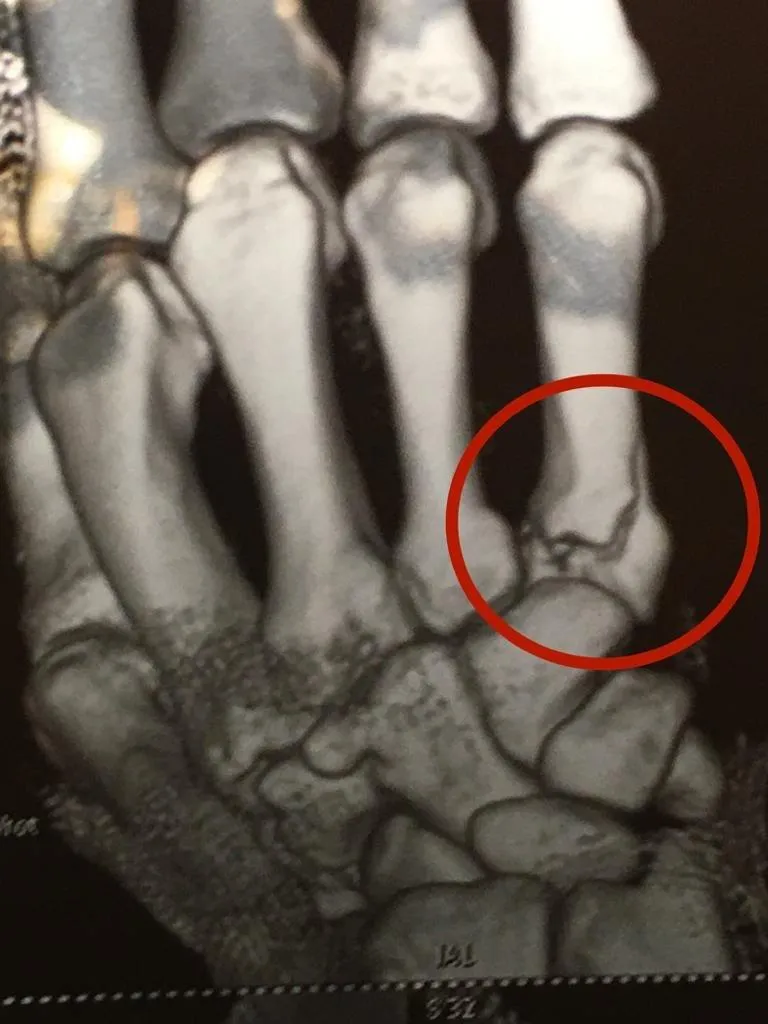

"Вже в другому раунді після чергової атаки суперника Артем відчув різкий біль у правій кисті руки і боксував з ним до фінального гонга. Після бою лікар турніру Юрій Дехтярьов надав нашому чемпіону невідкладну допомогу. На жаль, рентгенологічне обстеження підтвердило осколковий перелом п'ятої п'ясткової кістки в області її суглоба", – розповів медик.

Фото травми Артема Далакяна (фото: Чемпіон)

За його словами, на відновлення функції розбитого суглоба та проведення кваліфікованої реабілітації треба не менше двох місяців.

"Повноцінний тренувальний процес Артем зможе розпочати не раніше, ніж через три місяці.", – підсумував В'ячеслав Попов.